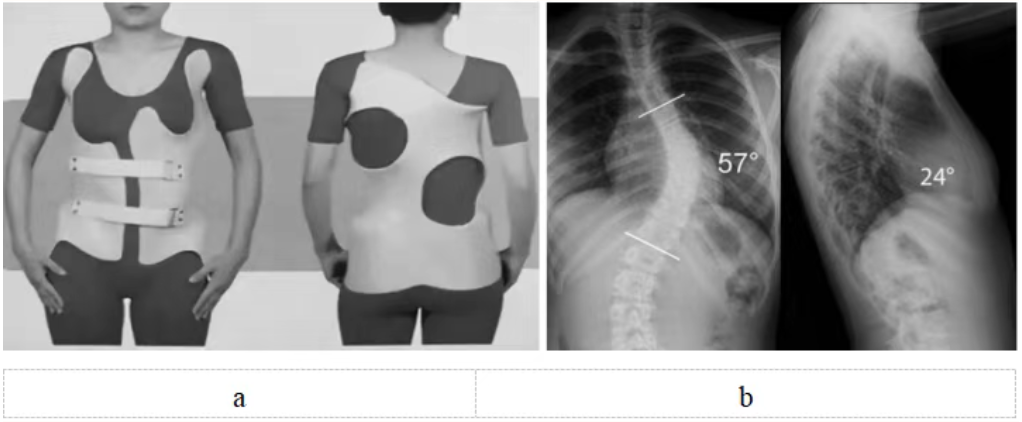

脊柱側(cè)彎支具治療需專業(yè)定制(圖5),日用型每天佩戴20小時(shí)以上,夜用型需整晚佩戴。初期可能有不適,需1~2周適應(yīng)期,要注意皮膚護(hù)理。必須堅(jiān)持佩戴至骨骼發(fā)育成熟,通常需要2~3年。矯正效果取決于佩戴時(shí)長(zhǎng)和持續(xù)性,家長(zhǎng)要做好監(jiān)督。

圖5 a:特發(fā)性脊柱側(cè)彎(中度)配戴支具正面觀和背面觀;b:特發(fā)性脊柱側(cè)彎(重度)X線正側(cè)位,需要手術(shù)治療。注:a和b非同一患者

重度側(cè)彎(Cobb角>40度)(圖5):